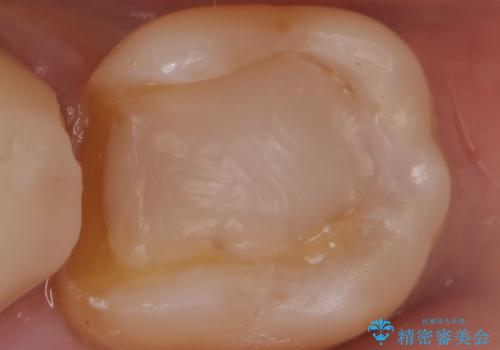

- 銀の詰め物を白くしたいとの事で来院。

銀の詰め物を外し、拡大鏡下でう蝕を全て取り除いたのを確認して

e-maxインレーにて治療しました。

セラミックの詰め物(e-maxインレー)は、銀の詰め物に比べて表面がツルツルしていて

表面の細菌が付着しにくいので、う蝕の再発リスクを下げる事ができます。

白い詰め物が入り希望に沿った処置となり大変満足して頂けました。